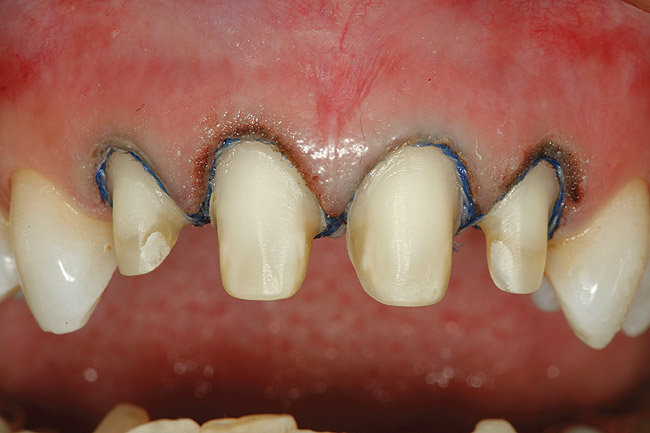

Figure 3  A gingivectomy was performed using an Er,Cr:YSGG laser to harmonize the soft-tissue levels. Biologic width was encroached upon and, therefore, a repositioning of the bony crest was also needed to prevent a relapse of the preoperative tissue position.

Figure 3

Figure 8  After initial closed-flap bony correction, a full-thickness mucoperiosteal flap was raised to visualize the accuracy of the osseous correction and observe the tooth surface and condition of the bony crest as a result of the procedure. It can be seen that the surface of the root is unscathed. The osseous crest was accurately repositioned 3 mm apically from the restorative margin, following its exact contour.

Figure 8

Figure 9  Facial view of tooth Nos. 7 through 10 after completion of the surgical phase of treatment.

Figure 9